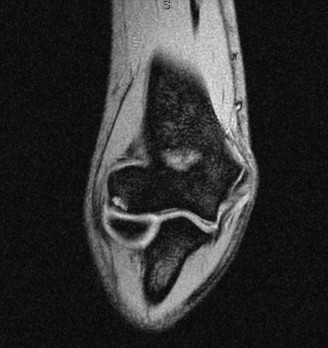

A 45-year-old carpenter presents with shoulder pain that has been ongoing for the last 3 months. He denies any significant injury. He describes night pain and significant discomfort at work. His imaging is shown in Figure 2–9. What is the most likely diagnosis?

🔍 Click to enlarge

🔍 Click to enlargeClinical Radiograph / Orthopedic Image

Figure 2–9_From Shi LL, Mullen MG, Freehill MT, et al. Accuracy of Long Head of the Biceps Subluxation as a Predictor for Subscapularis Tears. _Arthroscopy 2015;32(4):615–619.

Discussion

The correct answer is (A). Medial subluxation of the biceps tendon as seen in this MRI is commonly associated with a tear of the subscapularis tendon which attaches to the lesser tuberosity. This patient’s pain may in part be attributable to the subscapular tear and this should be evaluated for during physical examination. Supraspinatus tears (Answer B) cannot be easily visualized on axial views and are not associated with medial biceps subluxations. A labral tear and ALPSA lesion (Answers C and D) are not seen on the images provided. The question stem and MRI are not suggestive of shoulder instability (Answer E). Objectives: Did you learn...? Diagnose and treat acute rotator cuff tears?